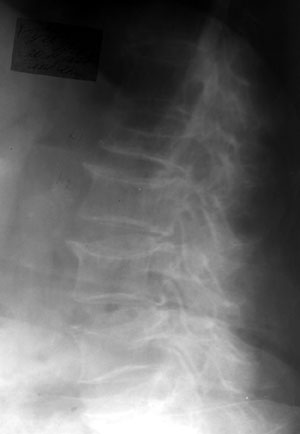

Остеопоротические деформации и переломы позвоночника у больных ревматоидным артритом.

Рис. 3. Компрессионная деформация LI .

Новости лучевой диагностики 2002 1-2: 20-22